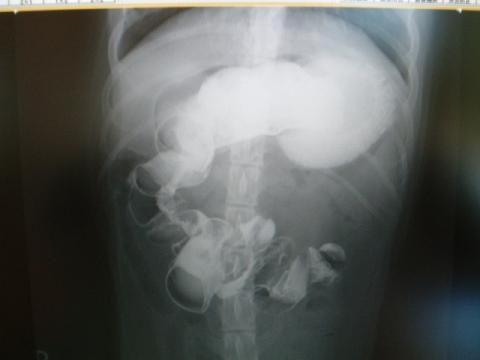

単純撮影では、大弯部で液体とガスの貯留による拡張が見られます。

小弯から幽門にかけて円形のマス陰影があります。異物でしょうか?

側面像での幽門洞のガス像の中にやはり不整形のマス陰影が見られます。

この写真は20分後です。

胃からの流れは停滞しており、真っ直ぐ尾側に下がるはずの十二指腸が縮れているようです。

2時間後の所見です。造影剤の流れは小腸の途中で止まっていて、明らかな腸閉塞所見です。

何よりも十二指腸がアコーディオン状に縮れ所見を示していて、これはひも状(線上)異物による

腸閉塞です。